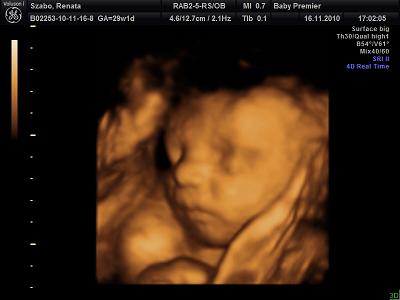

Köszönöm szépen a dícséretet. Igen én is beleszerettem a fülébe meg nekem a nózija az ami nagyon tetszik

Ez meg a szép mosoly,profilból!